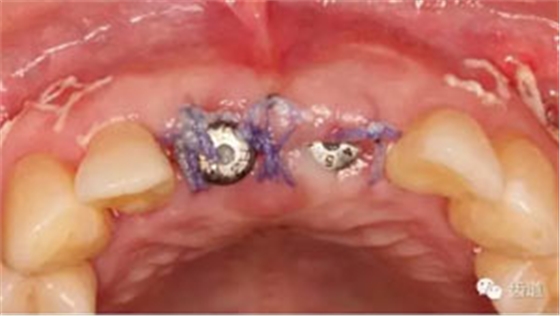

患者不愿才用自體骨移植,遂建議采用同種異體骨骨塊(皮質(zhì)骨)進(jìn)行骨環(huán)手術(shù)。 種植手術(shù):

修復(fù)治療: